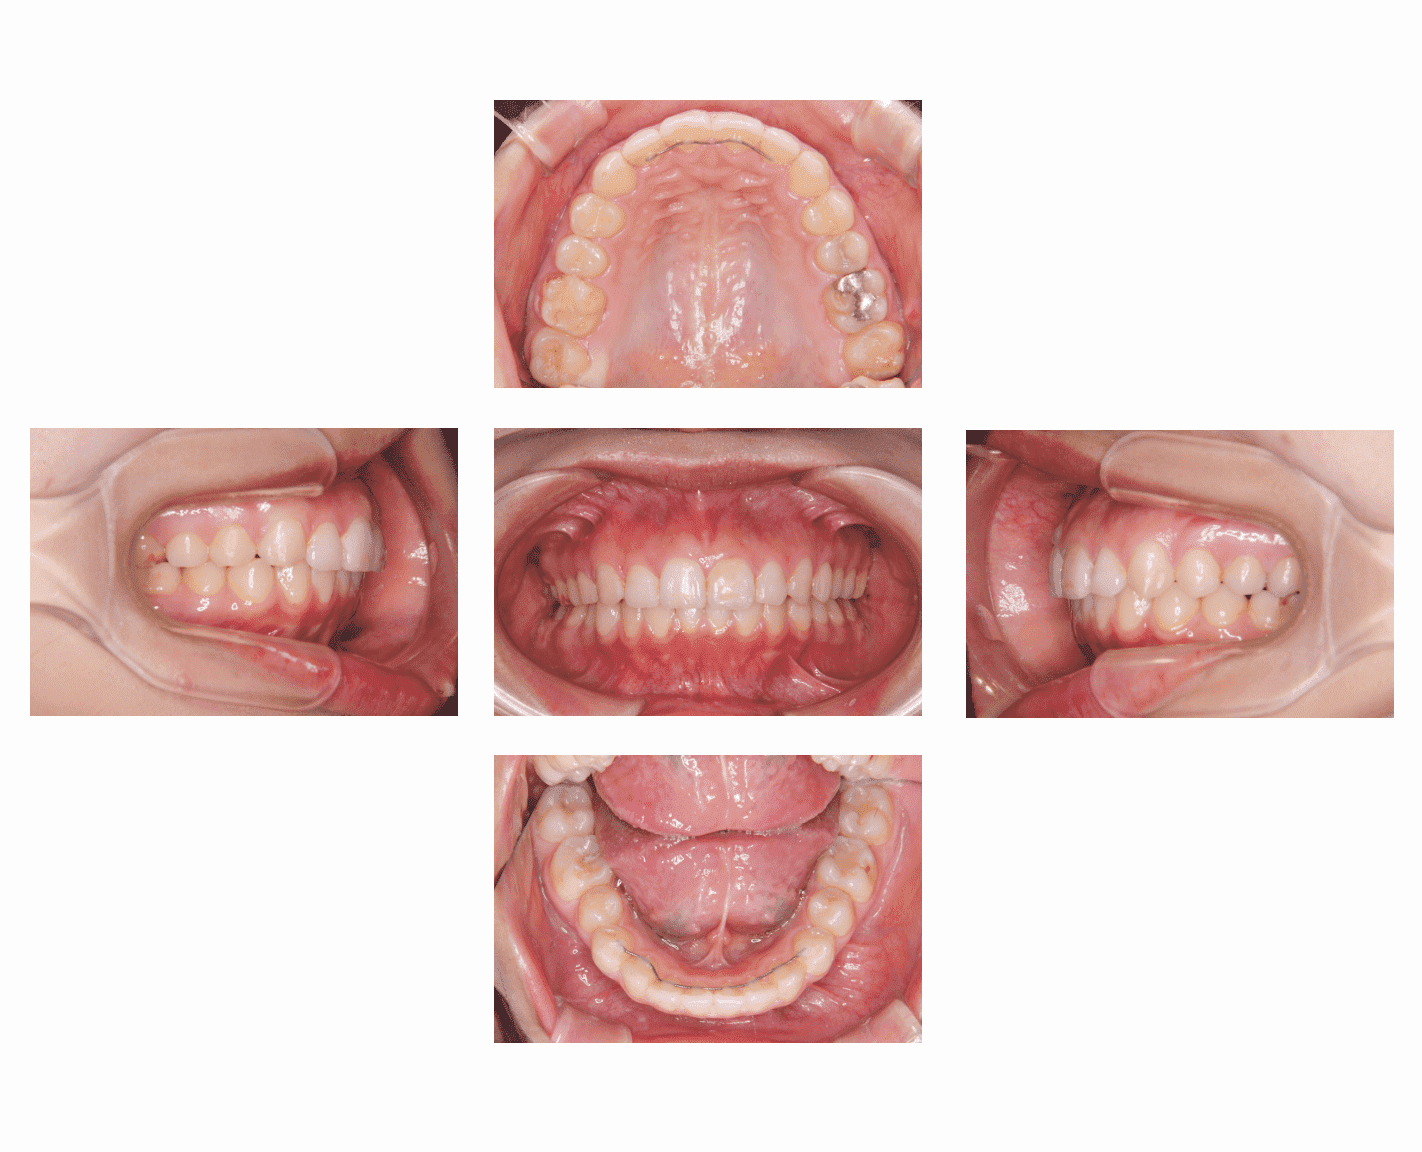

Case1

| 主訴 | 出っ歯が気になる |

| 診断名 | 上顎前突 |

| 年齢 | 27歳 |

| 治療に 用いた装置 |

リンガルブラケット矯正装置(エッグブラケット) |

| 抜歯部位 | 上下左右4番 |

| 治療期間 | 2年3ヶ月 |

| 治療費用 | 1,385,100円 |